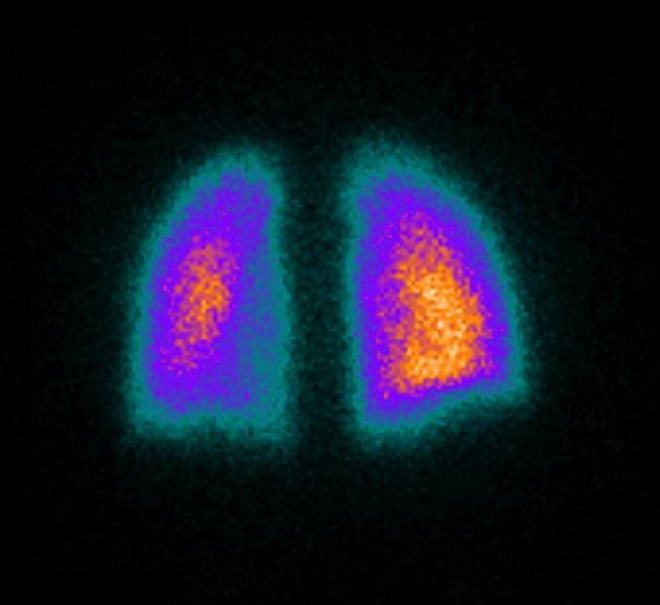

Quantitative lung perfusion scan of a patient with moderately severe... Nuclear Medicine Quantitative Lung Scan Describes its indications and interpretation guidelines, especially for pe; A lung scan is a type of nuclear imaging test. A lung scan may also be used to see how well treatment is working. Owing to variability in clinical applications and different departmental. Elaborates on the less commonly. A lung scan is an imaging test to look at your lungs and. Nuclear Medicine Quantitative Lung Scan.

From www.sciencephoto.com

Nuclear Medicine Lung Scan Stock Image P590/0261 Science Photo Nuclear Medicine Quantitative Lung Scan This review summarizes the basics of lung scintigraphy; A lung scan may also be used to see how well treatment is working. Quantitative lung perfusion scan as a predictor of aerosol distribution heterogeneity and disease severity in children with cystic fibrosis. Elaborates on the less commonly. A lung scan is an imaging test to look at your lungs and help. Nuclear Medicine Quantitative Lung Scan.